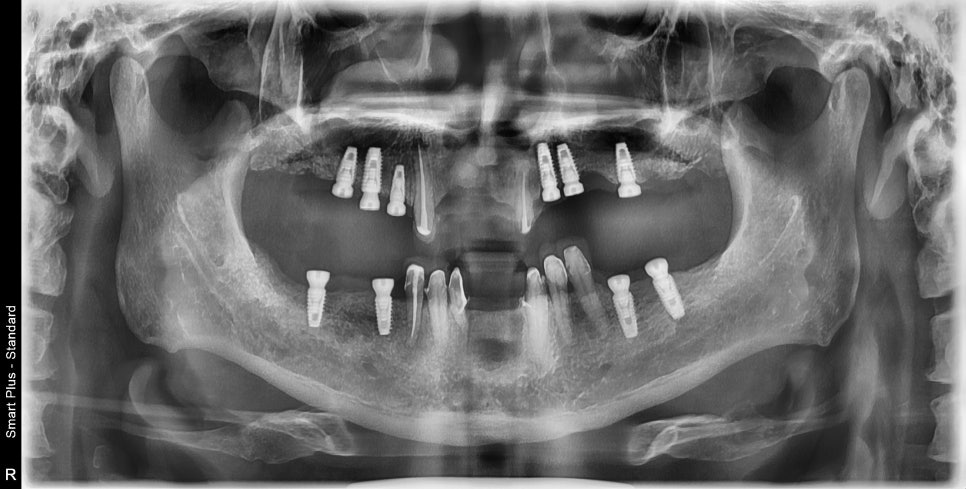

임플란트는 크게 2단계로 나뉠 수 있습니다

사진처럼 임플란트의 뿌리를 먼저 심고 기다립니다

그리고 뿌리가 충분히 굳는데는 3에서 6개월 정도 걸립니다.

경우에 따라서는 바로 다음단계인 보철물, 즉 임플란트의 머리를 올리는 과정으로 들어가는 경우도 있는데요

많은 연구 결과에서 뿌리를 심어두고 기다렸다가 머리가 올라가는것이 안정적이라는 보고가 있습니다.

저희도 필요에 따라서는 즉시하중임플란트를 시술하기도 합니다.